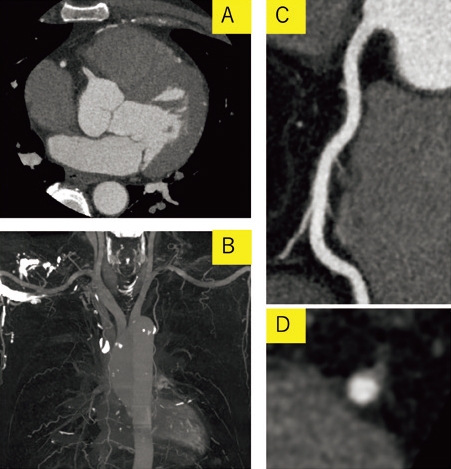

さらに、右心系や大動脈弓部に発生する造影剤のアーチファクトに対して、十分な量の生食を使用して後押しができるため、アーチファクトのない診断しやすい画像が得られる(図1、2)。

図2 生理食塩水後押しを行った画像

A:冠動脈CT Axial画像

B:大動脈MIP画像

C:右冠動脈CPR画像

D:右冠動脈短軸画像